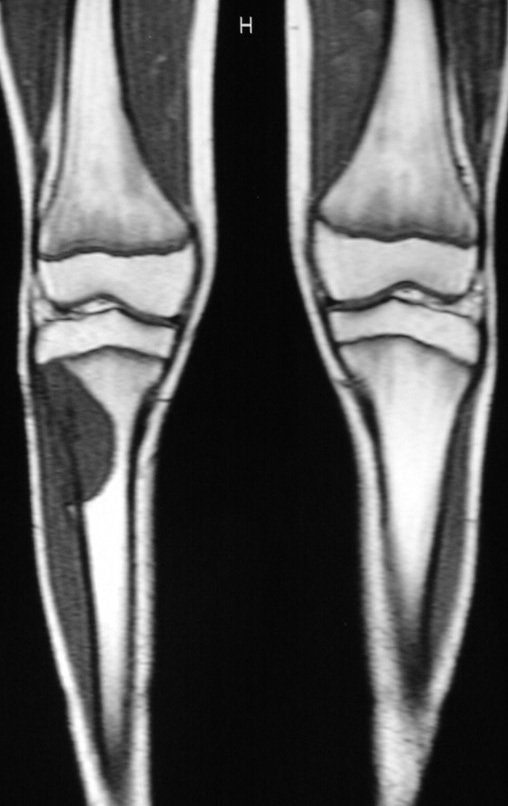

El autotrasplante del peroné vascularizado, con su placa de crecimiento, está demostrando ser una solución biológica eficaz. El peroné se “tibializa” y su placa de crecimiento continúa creciendo, reemplazando la placa de crecimiento tibial, que fue resecada junto con el tumor.

Miembro inferior alineado y clínicamente con la pierna más corta, ya que el acortamiento se produjo desde el inicio, debido a la inclinación de la epífisis, provocando deslizamiento inferior del vástago de la placa, ya demostrado con la inclinación de los tornillos epifisarios.